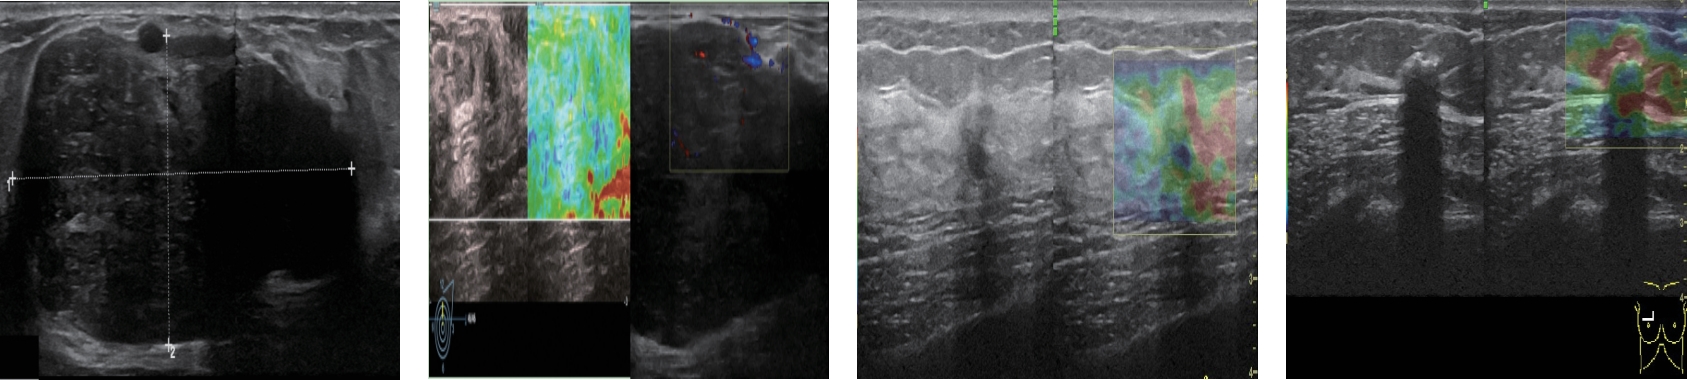

• 超声成像特征及超声血流参数鉴别Luminal型与三阴型乳腺癌的价值

2025, 35(16):21-27. DOI: 10.3969/j.issn.1005-8982.2025.16.004

摘要 (216) HTML (97) PDF 1.09 M (103) 评论 (0) 收藏

摘要:目的 分析超声成像特征及超声血流参数鉴别Luminal型与三阴型乳腺癌的价值。方法 回顾性分析2022年6月—2023年5月丽水第二人民医院收治的46例Luminal型与23例三阴型乳腺癌患者的临床资料,均行超声常规、三维灰阶模式及三维能量多普勒成像模式检查及免疫组织化学检测,比较两组的超声图像特征、血流参数变化。分析Luminal型乳腺癌的影响因素及超声成像特征、血流参数对Luminal型与三阴型乳腺癌的诊断效能。结果 Luminal型组圆形/椭圆形、边缘光整、血流分布呈环绕型的占比均高于三阴型组(P <0.05),后方回声增强占比、边界清晰占比、汇聚征发生率均低于三阴型组(P <0.05)。Luminal型组平均灰阶值(MG)、平均能量值(MP)、血管指数(R)、血管血流指数(VFI)均高于三阴型组(P <0.05)。多因素一般Logistic回归分析结果表明:形态[O^R=3.683(95% CI:1.283,10.577)]、边界[O^R=8.829(95% CI:3.018,25.830)]、边缘[O^R=2.910(95% CI:1.436,5.896)]、汇聚征[O^R=8.820(95% CI:1.849,42.062)]及MG[O^R=1.101(95% CI:1.010,1.200)]、MP[O^R=1.088(95% CI:1.000,1.183)]、R[O^R=6.780(95% CI:2.317,19.837)]、VFI[O^R=16.087(95% CI:5.498,47.065)]均为Luminal型乳腺癌的影响因素(P <0.05),受试者工作特征曲线结果显示,超声成像特征联合血流参数诊断Luminal型与三阴型乳腺癌的曲线下面积为0.967(95% CI:0.931,1.000),敏感性为97.80%(95% CI:0.892,0.993),特异性为95.70%(95% CI:0.875,0.989)。结论 Luminal型与三阴型乳腺癌患者的超声成像特征和超声血流参数具有不同的特点,具有较好的鉴别诊断价值,超声成像特征和超声血流参数可为乳腺癌的鉴别诊断提供参考。